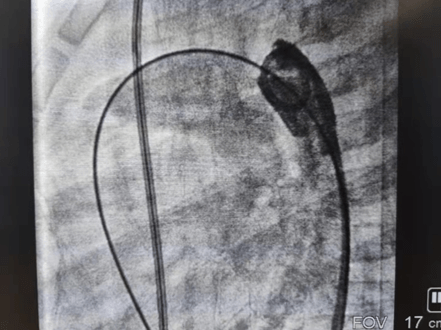

2021年11月12日,延安大學(xué)咸陽醫(yī)院心血管病院吳棟梁院長、李陽主任介入團(tuán)隊(duì)為一例年僅13個(gè)月的女性患兒進(jìn)行了先天性心臟病動(dòng)脈導(dǎo)管未閉介入封堵手術(shù)。這是我院迄今為止介入封堵治療年齡最小、體重最輕的患兒,手術(shù)過程順利,封堵成功,解決了一家人的痛苦,患兒術(shù)后恢復(fù)良好,于2021年11月17日順利出院。

先天性心臟病發(fā)病率已逐年下降,但因我國人群基數(shù)大,所以患者并不少見,先天性心臟病也是心血管疾病中為數(shù)不多的可通過介入或者外科手術(shù)得到根治的疾病之一,一般手術(shù)多建議在3歲以后進(jìn)行,3歲以內(nèi)患兒因體重太小,對(duì)患兒進(jìn)行動(dòng)靜脈穿刺置管、手術(shù)操作過程及麻醉難度明顯增加。該患兒體重僅10kg,身高僅70cm多一點(diǎn),因動(dòng)脈導(dǎo)管分流量較大,影響患兒發(fā)育,反復(fù)因肺部感染誘發(fā)心衰,并已經(jīng)出現(xiàn)左房左室擴(kuò)大,需盡早手術(shù),否則出現(xiàn)心衰加重可能錯(cuò)過手術(shù)時(shí)機(jī),但患兒家屬對(duì)外科開胸心存畏懼,而且外科手術(shù)后胸部手術(shù)瘢痕明顯影響女性患者的美觀,通過多方打聽,患兒聯(lián)系到了何克強(qiáng)醫(yī)生、李陽主任及吳棟梁院長手術(shù)團(tuán)隊(duì),家屬對(duì)醫(yī)生期望值極高,因患兒情況特殊,吳棟梁院長及心血管內(nèi)科五病區(qū)團(tuán)隊(duì)術(shù)前對(duì)患兒手術(shù)情況進(jìn)行討論,制定嚴(yán)密的手術(shù)方案,對(duì)手術(shù)中可能出現(xiàn)的難點(diǎn)進(jìn)行充分的準(zhǔn)備,最終在穿刺及麻醉成功后1小時(shí)內(nèi)便順利完成手術(shù),此例手術(shù)的開展,標(biāo)志著我院在先心病介入治療方面再上新臺(tái)階,患兒術(shù)后恢復(fù)非常好,得到了患兒家屬的肯定,解決了患兒一家的困擾。